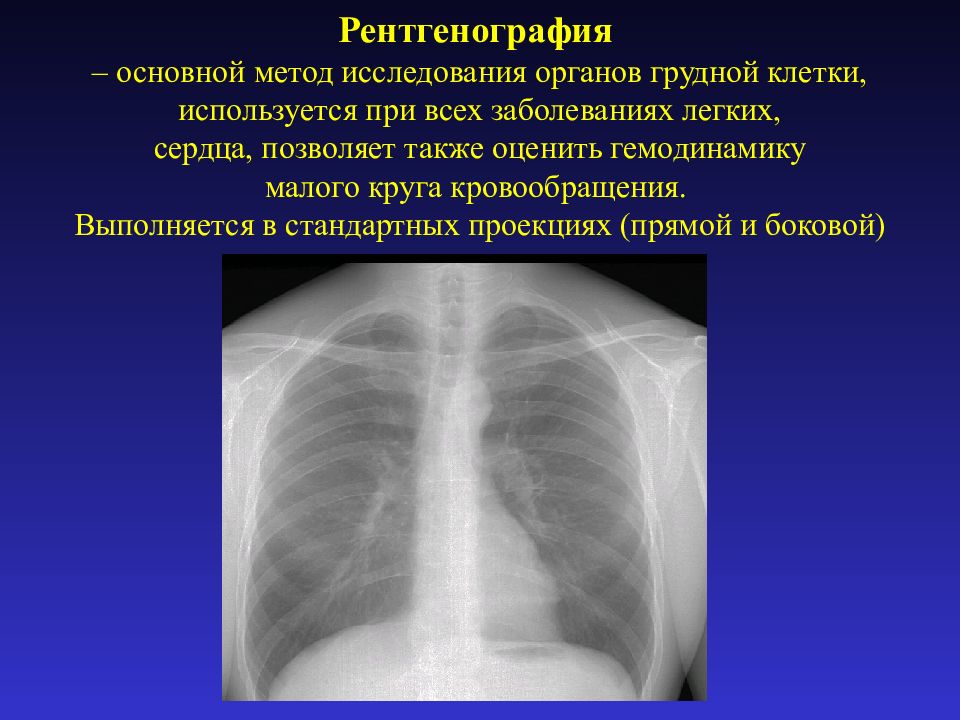

Рентгенологические изображения и синдромы патологии легких

Раздел: Кадры-подсказки